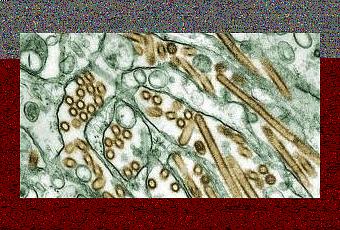

Près d'un an après se l'être imposé, chercheurs sur la grippe mettent fin au moratoire des expériences controversées impliquant le virus de la grippe aviaire H5N1. La « controverse » H5N1, débutée fin 2011 –avec le développement en laboratoire d'un supervirus hautement pathogène et transmissible à l'Homme- avait déjà pris un tournant lors des publications respectives, en mai et juin dernier, dans les revues Nature et Science, de la première des 2 études bloquées depuis janvier par les autorités américaines et d'un bilan consacré aux recherches déjà menées. Ces publications alertaient ou informaient pleinement de la menace potentielle posée par ce virus à l'humanité et montraient tout l'intérêt de ces recherches pour la santé publique. La controverse aura aussi imposé entretemps, d'entamer la révision, sous la gouverne de l'OMS, des mécanismes de validation de principe de telles recherches et incité les États-Unis et d'autres pays comme les Pays-Bas, à imposer une plus grande surveillance aux recherches sur H5N1. Ainsi, en décembre dernier, les experts des US National Institutes of Health, confirmaient, à l'issue d'une réunion de 2 jours, leur décision de mettre fin au moratoire.

Source: Science Online January 23 2013 DOI: 10.1126/science.1235140 Transmission Studies Resume for Avian Flu (Visuels CDC)